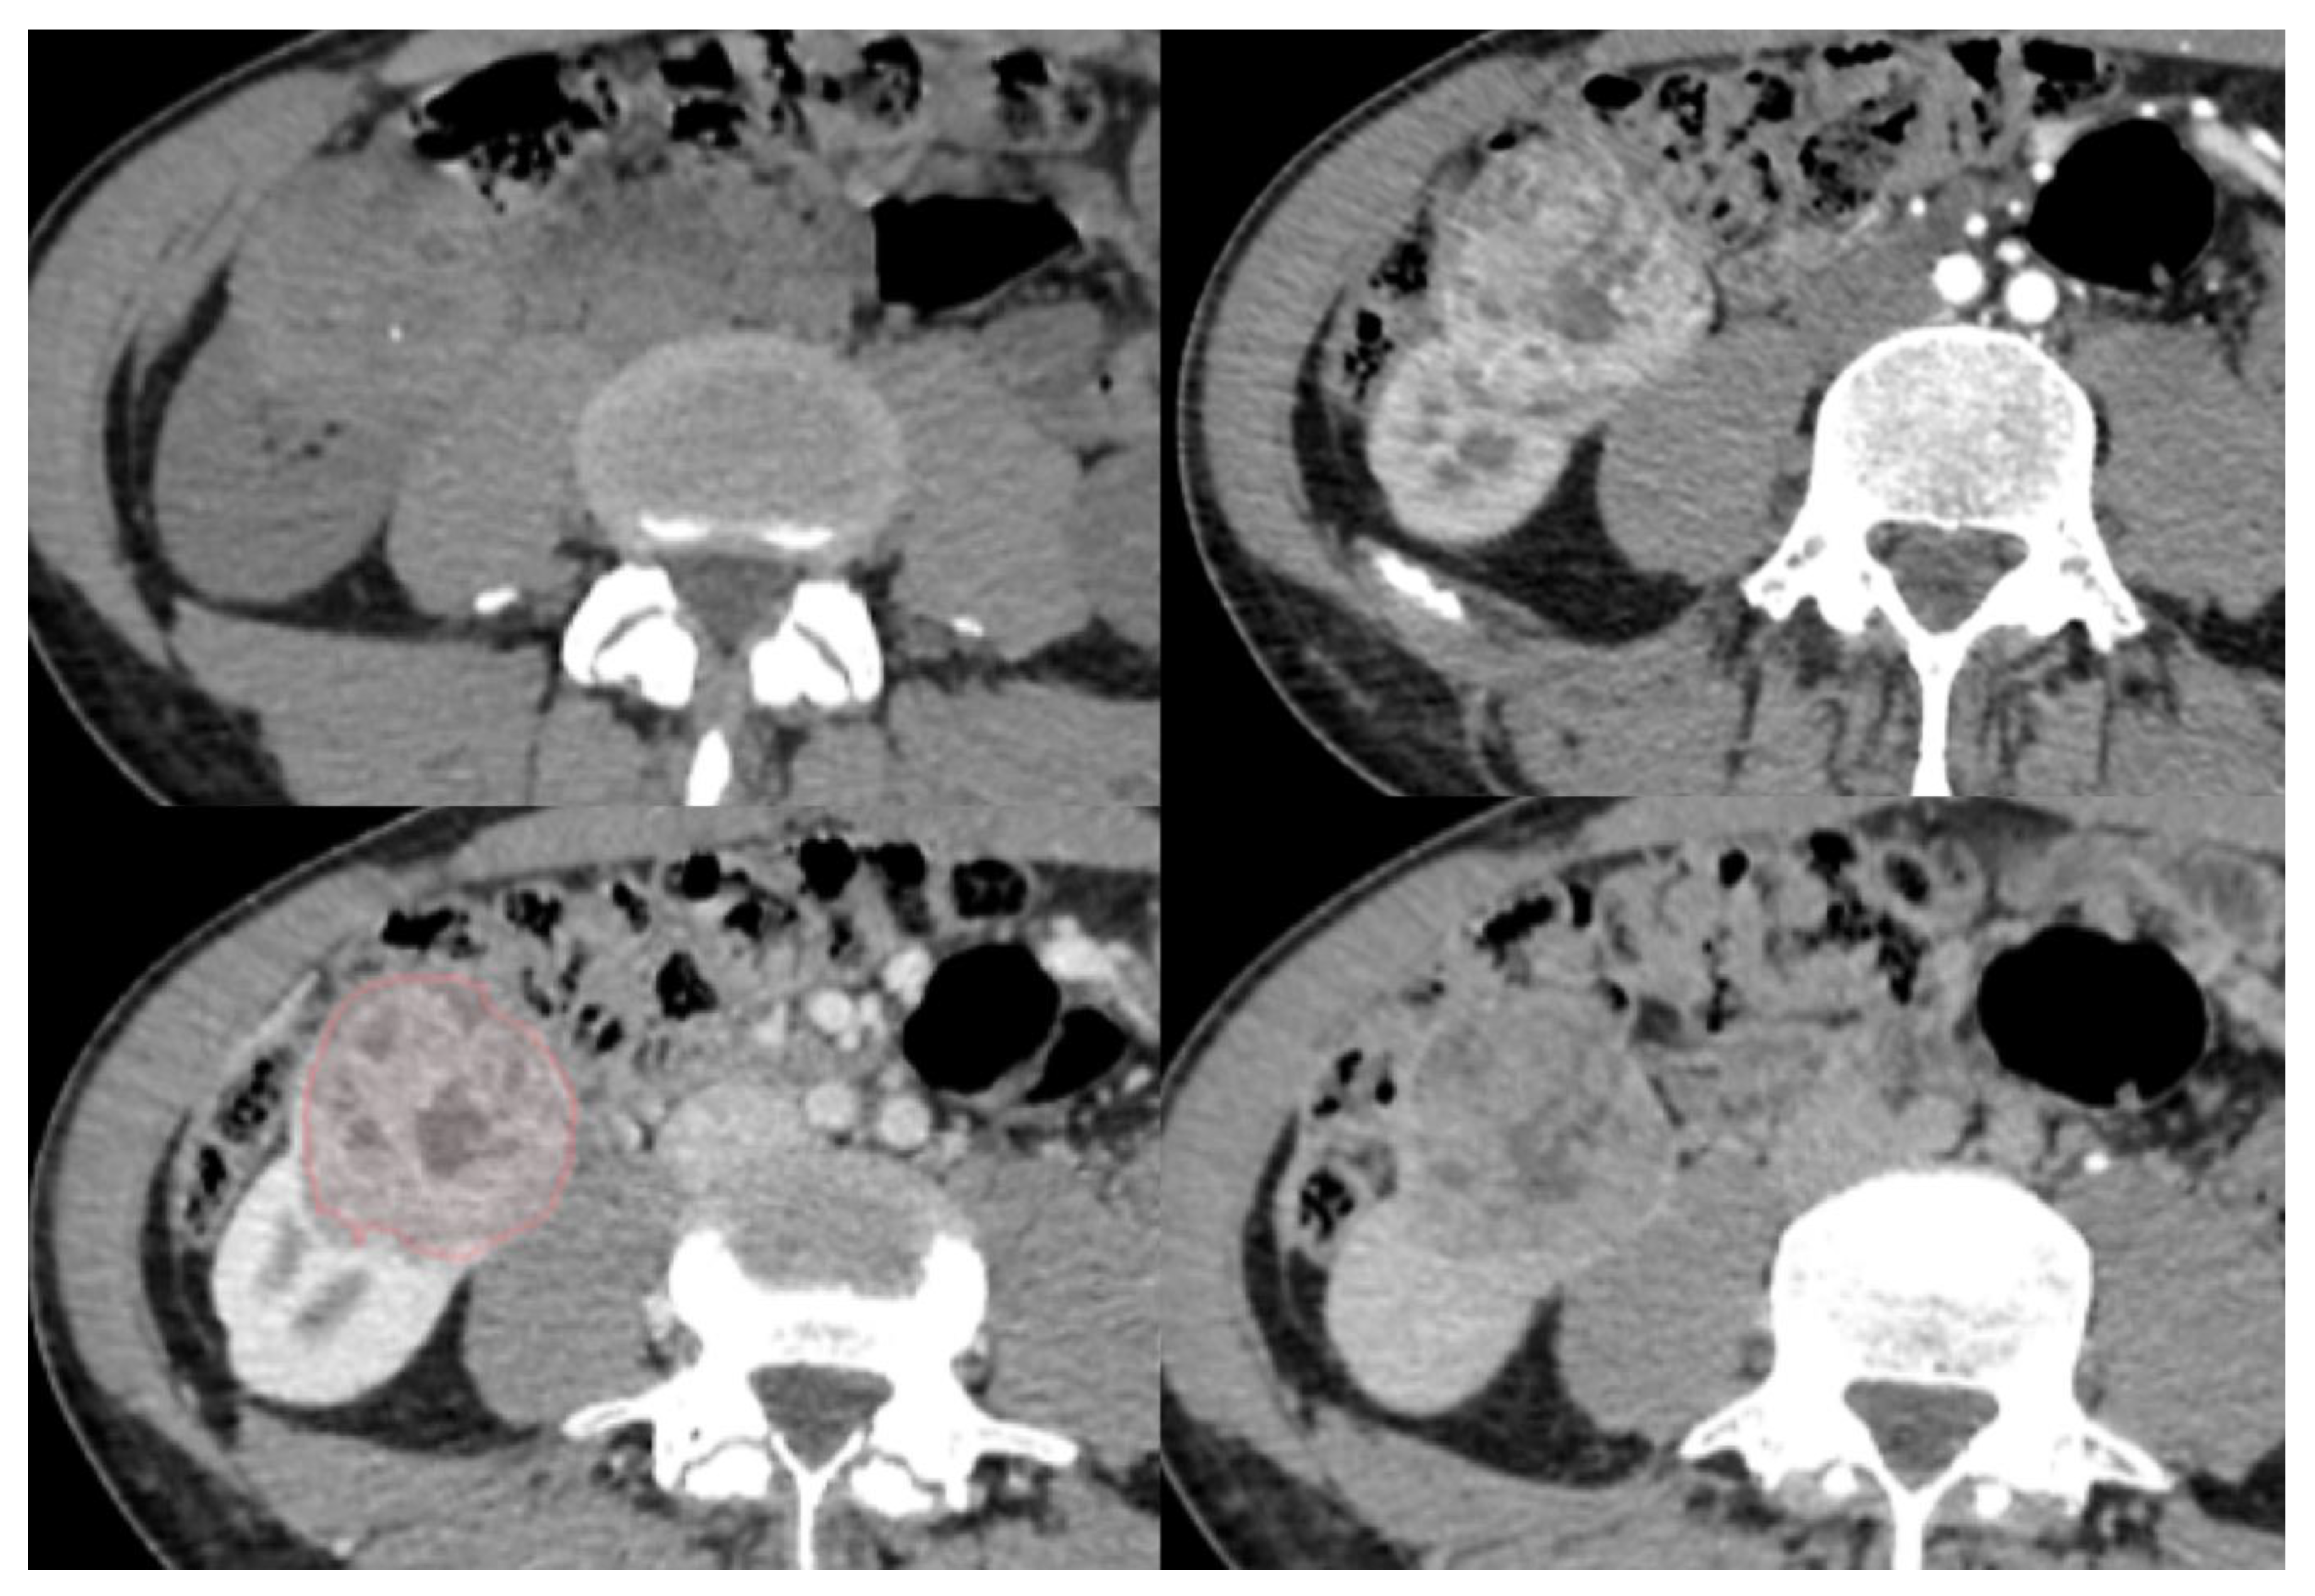

2.2. CT Examinations

2.3. CT

3.2. Conventional and Enhanced Radiological Features

3.3. Three-Dimensional Radiomic Features